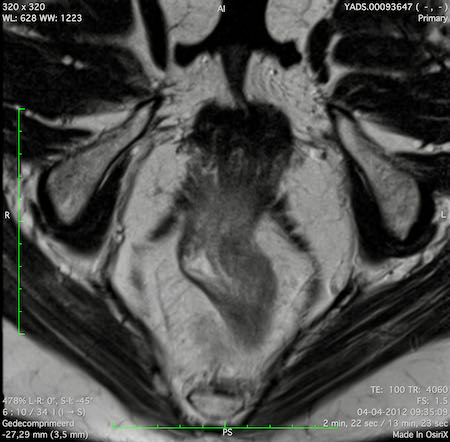

Đặc điểm MRI

- Thường khó xác định

- Thường biểu hiện nhưdày thành ruột lan tỏa, đoạn dài

- Kiểu tăng trưởng dưới niêm mạc, cho ra mộtHình ảnh “bia” (target)trên các hình ảnh cắt ngang

- Thâm nhiễm mỡ trực tràng lan tỏalà phổ biến

Hình ảnh

Các hình ảnh được cung cấp cho thấy ung thư biểu mô tế bào nhẫn với tình trạng dày lan tỏa thành trực tràng, hình ảnh bia bắn điển hình, và sự xâm lấn mỡ mạc treo trực tràng.